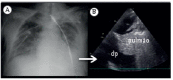

Lung ultrasound in the evaluation of pleural effusion